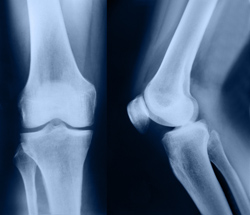

Implantes tisulares para lesiones de rodilla

Los meniscos de la rodilla proporcionan a la articulación la integridad estructural que necesita cuando está sometida a tensión o torsión. Un equipo de investigadores ha probado la regeneración de los tejidos de esta parte vital de la rodilla en un modelo animal, en un intento de evitar el dolor y el deterioro comúnmente asociados con lesiones.

En el deterioro de la articulación de la rodilla se encuentran a menudo implicados uno de los dos meniscos, las estructuras cartilaginosas que reparten las cargas impuestas por el cuerpo durante el movimiento. Tanto el desgaste que acompaña a la longevidad como las lesiones deportivas a menudo conducen a lesiones que pueden acabar en dolor crónico, osteoartritis y dificultades de movimiento, con la consiguiente pérdida de calidad de vida. Con el fin de encontrar una alternativa a la resección del tejido dañado, el proyecto MENISCUS-REGENERATIO, financiado por la UE, se fijó el objetivo de desarrollar protocolos de cirugía para sustituir el tejido con materiales de bioingeniería. El menisco se construiría utilizando un «andamio» o matriz bioactiva y células autólogas. En los ensayos de implantes en ovejas se utilizó el biomaterial desarrollado por los socios del proyecto. Un estudio piloto con ocho ovejas ofreció resultados prometedores. Los implantes permanecieron en su sitio y se integraron en la cápsula de la articulación. A las seis semanas se había formado tejido con todos los tipos de células y su correspondiente vascularización. Además, no había signos de alergia o de respuesta inmune. Sobre esta base, el equipo del Istituti Ortopedici Rizzoli (Italia) amplió las pruebas para incorporar a dos grupos de un total de sesenta y cuatro ovejas evaluadas a lo largo de doce meses. Los investigadores compararon dos técnicas quirúrgicas e implantaron andamios o bien libres de células o sembrados con condrocitos articulares. La evaluación se basó en marcas diseñadas específicamente para el proyecto, una para la integración del implante, con nueve categorías, y otra para los cambios en la articulación, que evaluaron doce áreas diferentes de ésta. También se evaluaron los implantes desde el punto de vista histológico respecto a todos sus componentes celulares y tisulares, factores importantes como la presencia de residuos del andamio o de células indicadoras de una respuesta inflamatoria incluidos. La gran cantidad de datos recopilados sugiere que el andamio de hidroxiapatita y policaprolactona (HA-PCL) es un candidato prometedor, ya que dio muestras de tolerancia inmunológica e indujo el crecimiento del tejido. Sin embargo, se han encontrado problemas con las propiedades mecánicas y la técnica de de fijación del implante, por lo que se planea seguir investigando para eliminar estas limitaciones. La investigación ha sentado la base para el desarrollo de un implante que podría aplicarse quirúrgicamente en caso de meniscos dañados. La reconstrucción de una articulación sana in situ sin necesidad de una resección completa significa un periodo mucho más corto de recuperación y una mayor probabilidad de que se produzca el restablecimiento completo.